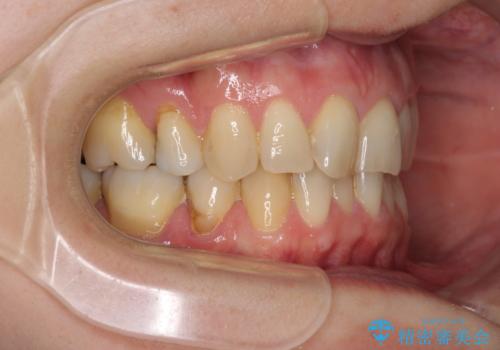

- 上下前歯の叢生を気にして来院された患者様です。

費用を抑え、期間もあまりかけずに治療をしたいとのことで、インビザライン・ライトを用いて矯正治療を行うこととしました。

矯正治療後には、下顎臼歯の目立つ銀歯をセラミックインレーにて修復治療を行いました。